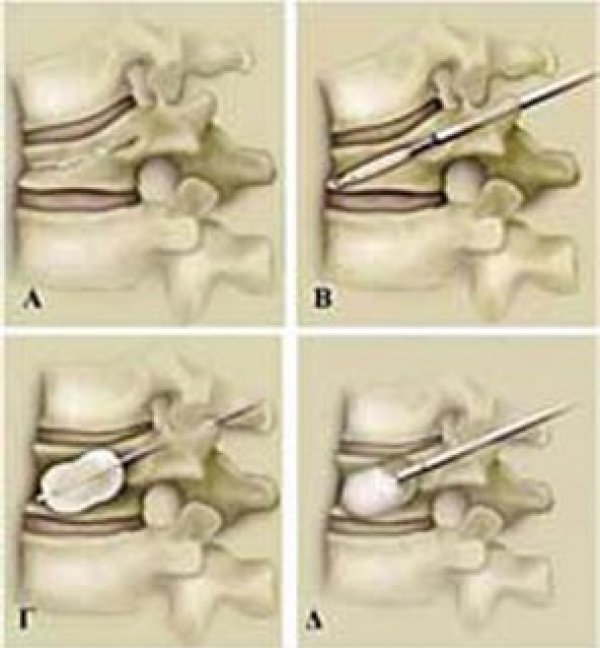

Προϊόντα / Υπηρεσίες Αρθροσκοπική Χειρουργική γόνατος, ώμου, ποδοκνήμης Αθλητικές Κακώσεις Αρθροπλαστική Ελαχίστης Επεμβατικότητας μικρών τομών Χειρουργική Σπονδυλικής Στήλης Ρομποτική Χειρουργική Παθήσεις του γόνατος Παθήσεις του ισχίου Παθήσεις του άκρου ποδός Παθήσεις του ώμου Παθήσεις του χεριού Παθήσεις της σπονδυλικής στήλης Κατάγματα